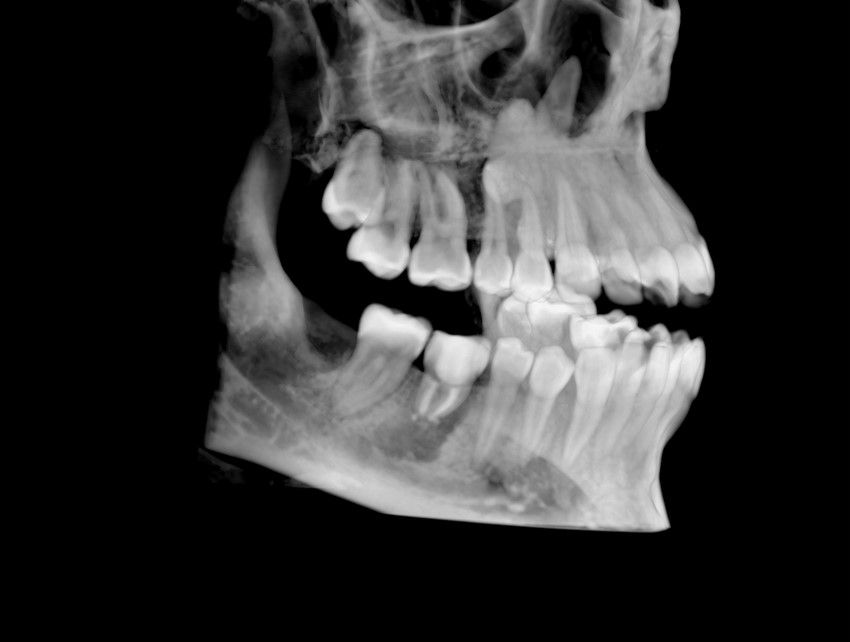

El autotrasplante dental es una opción terapéutica para aquellos casos en la que una pérdida dentaria es reemplazada por un diente donante del mismo paciente. Este autotransplante colocado en el alveolo puede ser inmediato o diferido. Suele estar indicado en paciente joven, siendo más frecuente el autotransplante de cordal a primer o segundo molar, y el de premolar a incisivo. El diente donante debe reunir unos criterios clínicos que aumenten el éxito de la técnica, basados en la morfología, el estadio de desarrollo radicular y la salud periodontal. La planificación se llevará a cabo con un CBCT y simulación virtual que genere un prototipo réplica en 3D; esto permite evaluar las dimensiones del diente donante para su correcta colocación en el alveolo receptor.

Se reporta el caso de un autotrasplante del tercer molar inferior derecho al alveolo postextracción de un primer molar inferior, en una paciente de 22 años de edad. Actualmente, el autotransplante se considera una opción de tratamiento si se siguen los criterios de selección del caso adecuados, y se realiza una técnica quirúrgica protocolizada. El diagnóstico planificado mediante CBCT, la simulación virtual y la confección de una réplica en 3D optimiza la técnica de forma segura, predecible con tiempos de cirugía menores.

El sitio receptor debe garantizar la adaptación del diente donante, se realizará un diagnóstico mediante planificación con CBCT que permita segmentar virtualmente el diente donante y llevarlo digitalmente al sitio receptor3.